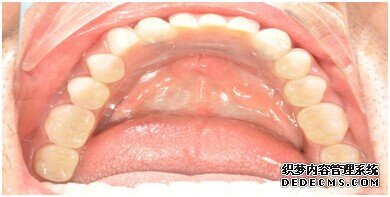

种植设备检查牙齿

整个种植牙完成后的效果图

种植牙整个过程完成后,刘女士非常满意自己的牙齿,并且表示以后一定会遵照医生的嘱咐好好注意自己的口腔健康,每晚一定会好好刷牙,饭后漱口,当然也会注意保护这颗种植牙!